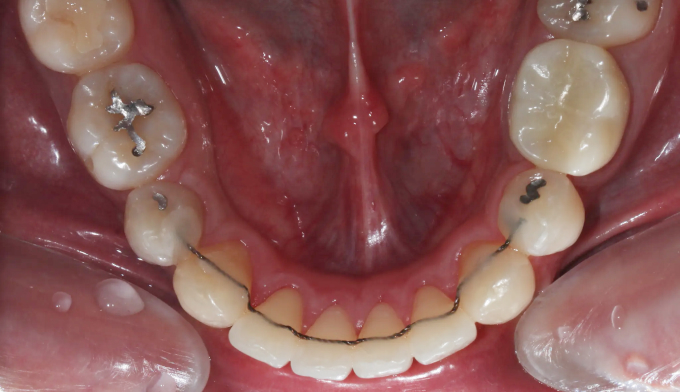

돌출감과 가지런하지 못한 앞니, 그리고 어금니의 교합이 좋지 않은 경우입니다.

좌측 아래 작은어금니가 빠진이 오래되었기 때문에, 균형을 맞추기 위해 반대편 작은어금니를 발치하여 돌출감을 해소해주었습니다. 나왔던 입이 들어가면서 턱 라인이 개선되었고, 입을 다물때도 보다 더 편안하게 되었습니다.

교정전부터 변색되어있던 양쪽 앞니는 미백과 보철치료를 동반하여 교정종료 후 개선하였습니다.

총 교정치료는 22개월입니다.